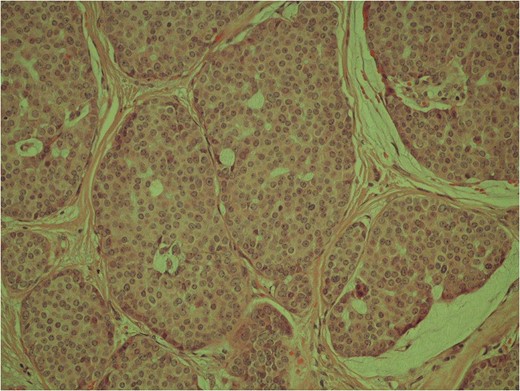

High power image of the dermal nests of tumour showing solid islands of invasive breast carcinoma.